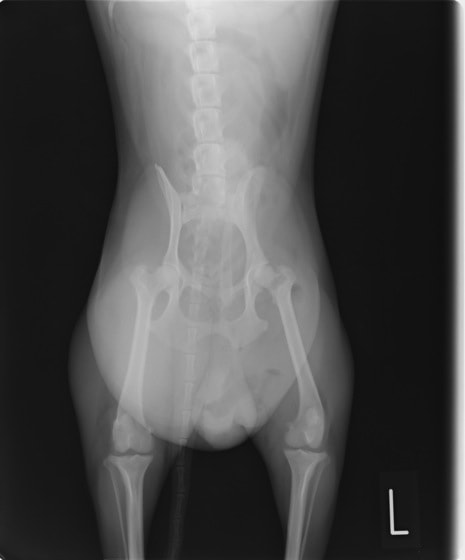

■ 症例 1歳 アメリカンショートヘア 未去勢雄

高所から誤って落下し、ぐったりしていることを主訴に来院。来院時低体温・意識レベルの低下あり。

血液検査にて高窒素血症、高カリウム血症(K:7.0mEq/L)を認めました。レントゲン検査にて膀胱内にガス貯留を認めました。

エコー検査にて腹水貯留を認め、エコーガイド下で穿刺を行い腹水が尿であることを確認しました。

高カリウム血症による心停止が考えられたため、静脈点滴やインスリン投与によるカリウム値の補正を試みましたが、反応はなく数値の悪化(K:8.9mEq/L)が認められました。しかし、水和状態や体温・意識レベルの回復が認められたため、緊急手術を実施しました。